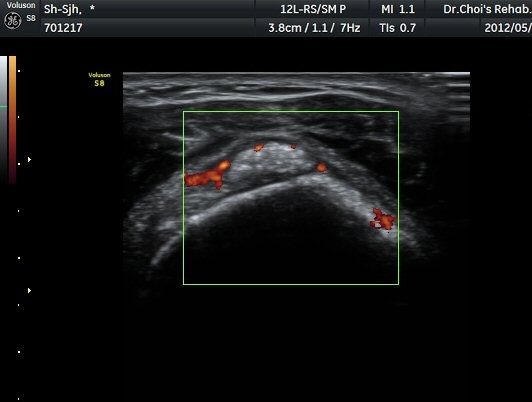

ÆÄ¿öµµÇ÷¯ °Ë»ç¿¡¼­ Ç÷·ùÁõ°¡¸¦ º¸ÀδÙ(»çÁø 6).  Ⱦ´Ü¸é°Ë»ç¿¡¼­µµ °í¿¡ÄÚ µ¢¾î¸®¿Í

Ç÷·ùÁõ°¡°¡ È®ÀεȴÙ(»çÁø 7, 8).